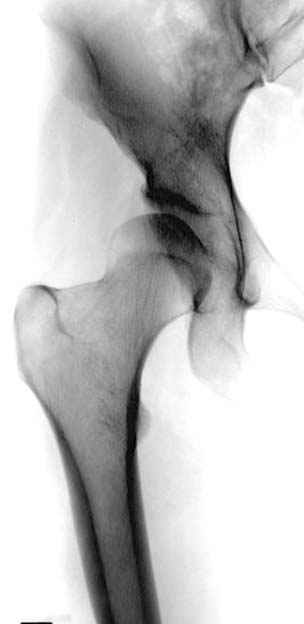

Модель несовершенна, согласен, однако я экспериментировал и с импровизированной илеофеморальной связкой и ацетабулярной губой. Результат был тот же, подвижный узел замыкался посредством аналога СГБ. Для интереса я прилагаю фото., где сымитированы наружные связки и вертлужная губа, но без СГБ видно по показаниям динамометра, что данные структуры незначительно только на 0.5 кг разгружают аналог отводящих мышц. Почему модель получилась именно такой можно рассказать и подробнее если захотите…